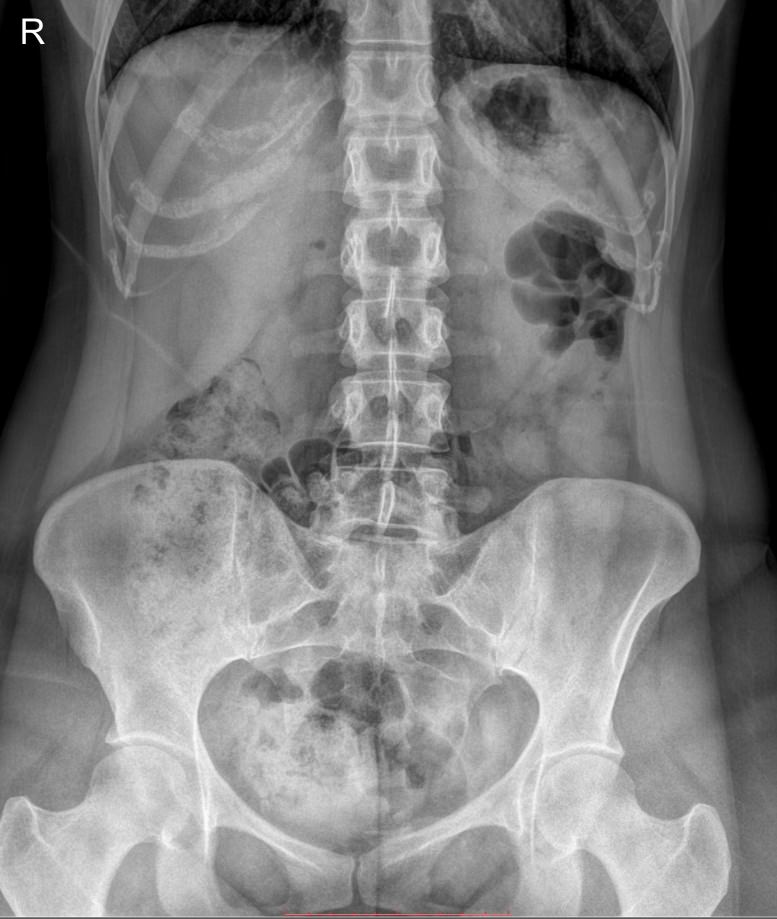

Рентген почек, мочеточников, мочевого пузыря (обзорный)

Обзорный снимок мочевыделительной системы обычно является первым этапом в ее диагностике. Часто он предшествует экскреторной урографии, но может быть и самостоятельной процедурой. Современное цифровое рентгеновское обследование основано на тех же принципах, что и аналоговое прошлых поколений. То есть в результате исследования мы получаем классический черно-белый снимок. Но сейчас для диагностики применяется минимально возможная доза облучения, которая позволяет безопасно делать несколько снимков подряд. Именно такое оборудование используют в клинике «Доступная медицина».

Что показывает обзорный рентген мочевыделительной системы

У здорового человека обзорный снимок покажет:

- Тени почек и мочевого пузыря;

- Мочеточники ― только при значительных изменениях;

- Нижние грудные, поясничные позвонки, ребра, тазовые кости;

- Тени поясничных мышц.

На рентгенограмме будут видны такие патологии, если они есть:

- Увеличение или уменьшение почек в размерах ― признак врожденной аномалии, воспаления и других заболеваний;

- Камни в почках и мочевом пузыре;

- Коралловидные камни в почках;

- Конкременты в желчном пузыре;

- Флеболиты ― камни вен малого таза;

- Опухоли и очаги склероза в костях малого таза;

- Обызвествленные хрящи ребер и лимфоузлы;

- Инородные тела.